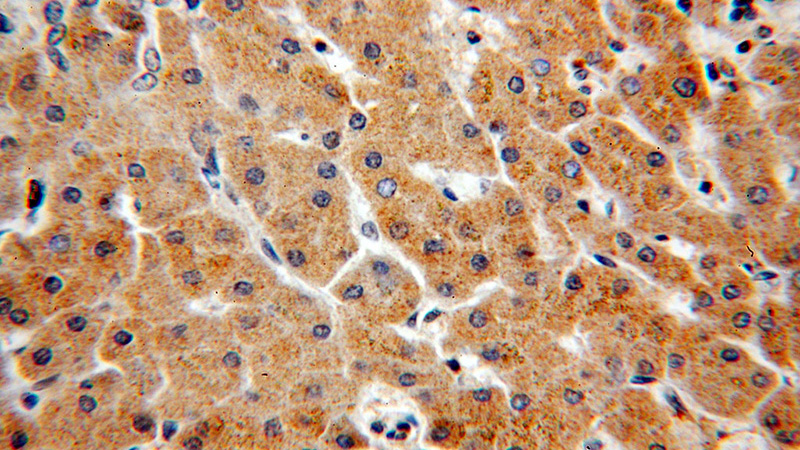

Immunohistochemical of paraffin-embedded human hepatocirrhosis using Catalog No:109706(CYP4F11-Specific antibody) at dilution of 1:50 (under 40x lens)